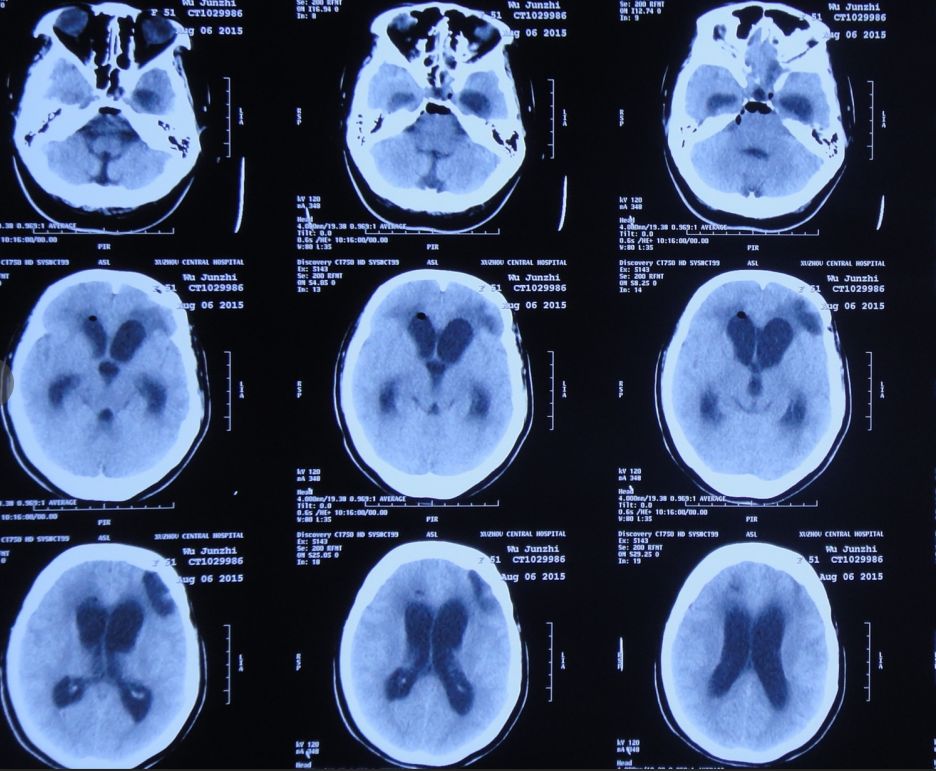

2015年8月6日,复查头CT:脑室显著扩张,室旁水肿明显,颅内积气(图15)。患者仍有脑脊液鼻漏,但当地医院不予脑脊液漏修补治疗。

图15:2015年8月6日头CT:脑室显著扩张,室旁水肿明显,颅内积气